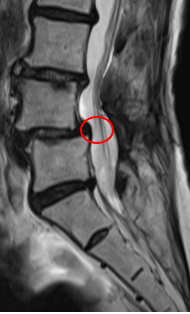

治療後

腰痛と、左下肢の痛み・痺れの根本原因であるL4/5の狭窄を取り除く手術「PEL」を施し、神経の圧迫を取り除きました。またこの手術時には、神経細胞の修復作用効果を期待して、濃縮血小板由来の成長因子を患部に注入する再生医療「PRP療法」を行いました。

┃治療後の経過

手術の翌日には痛みと痺れが軽減。椅子から立ち上がるときに痛みを感じなくなるほど回復しました。術後2か月経過時には主症状に挙げていた痛みは手術前と比べて10から1に、痺れは10から0になりました。